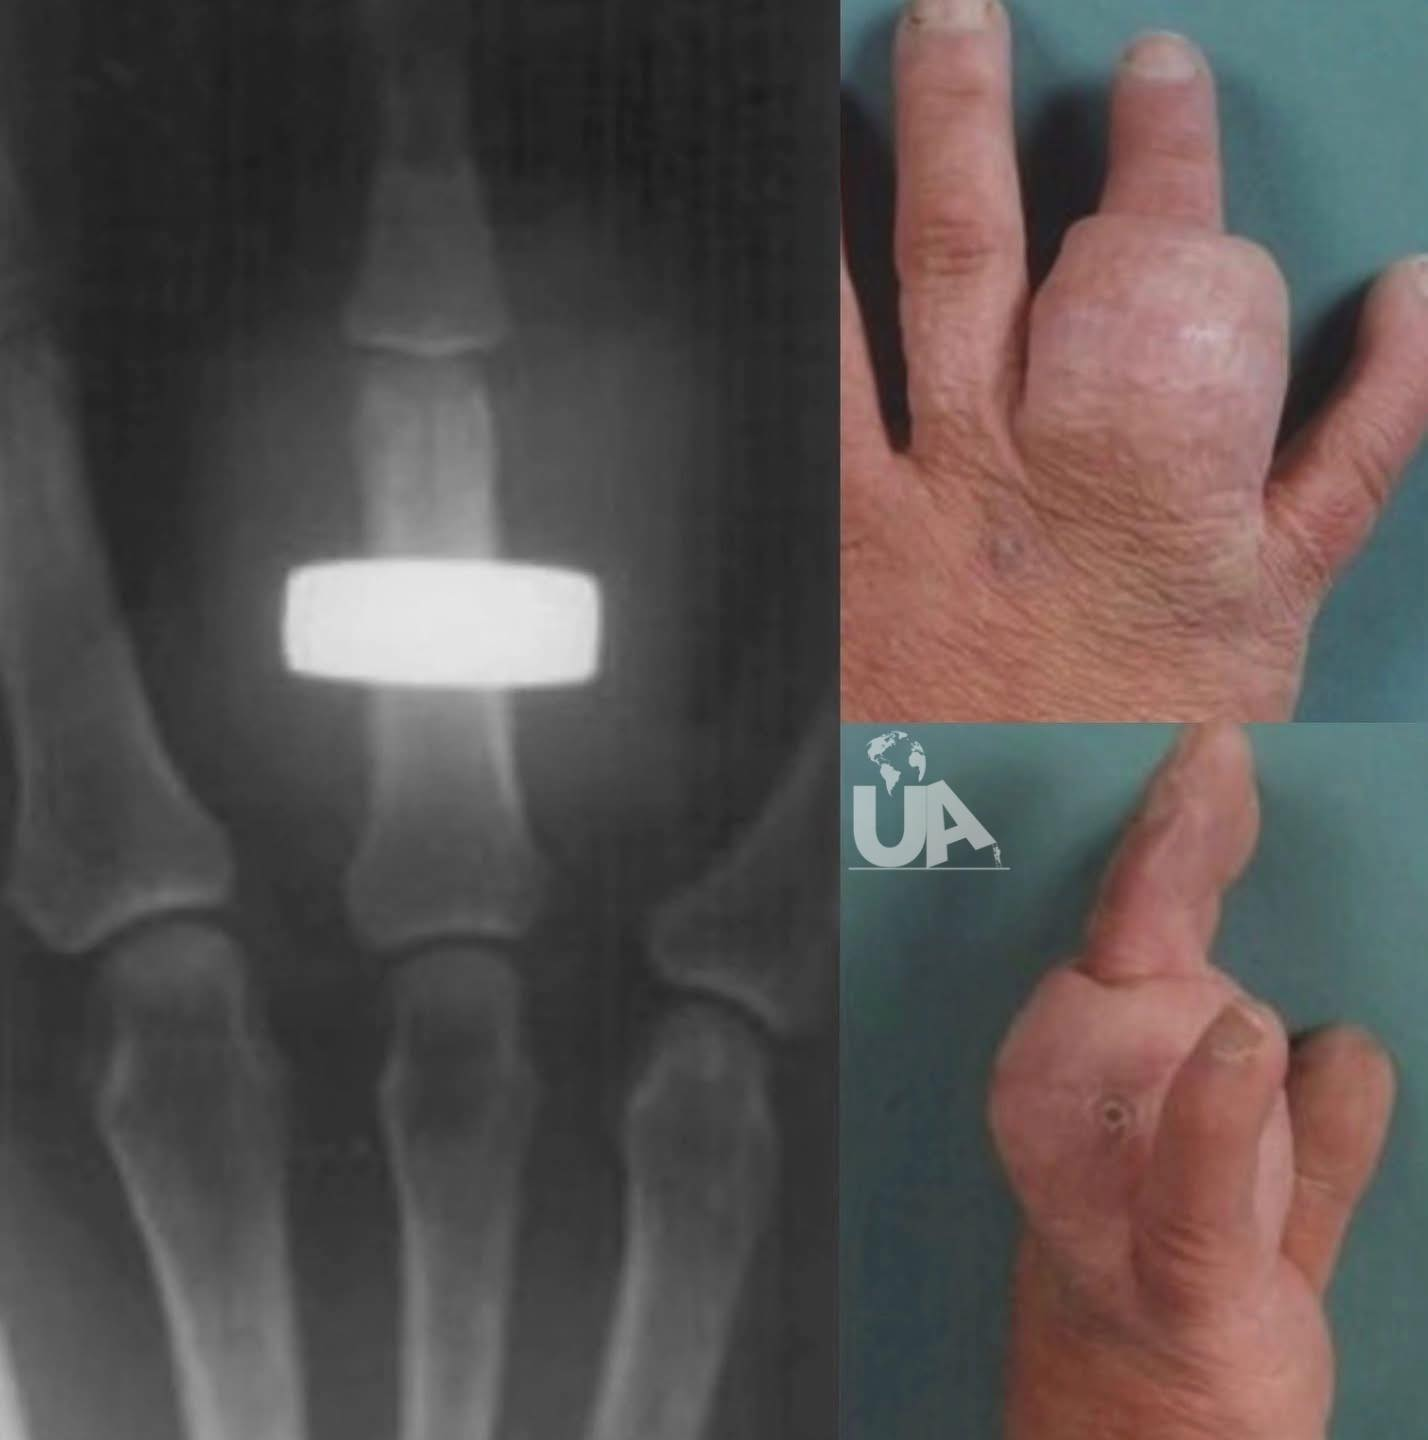

Lo que parecía solo una hinchazón terminó siendo un caso que dejó a más de un médico con la boca abierta 😧. Una mujer con hipotiroidismo y esquizofrenia fue atendida por una protuberancia en el dedo anular… pero la radiografía reveló algo insólito: un anillo de bodas enterrado bajo la piel.

Al parecer, su condición médica le impidió notar o atender el problema. El anillo se encontraba envuelto completamente en tejido blando, como si el cuerpo lo hubiera absorbido poco a poco.

Además, la paciente tenía anemia y una infección ligera por estafilococos, lo que causaba aún más inflamación. Fue necesario realizarle una cirugía para extraer el anillo, que ya no se podía ver a simple vista.